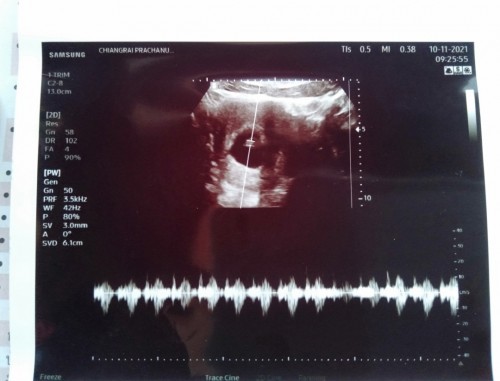

กี่ weeks ถึงจะตรวจเจอการเต้นของหัวใจลูกน้อยคะ

ตอนนี้น้อง 6 weeks 2 days